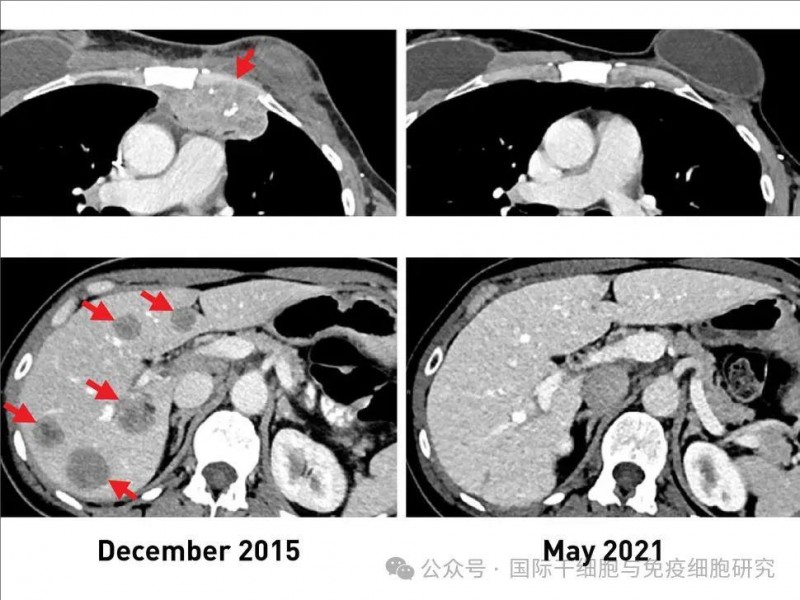

这位患者在接受TIL细胞治疗前,已出现胸壁(左上)、肝脏(左下)转移病灶,入组接受TIL细胞治疗后,肿瘤完全缩小(详见下图),她幸运地获得了完全缓解(CR)。更为惊喜的是,治疗5年后复查影像学显示,她至今仍未患癌症。

▲图源NCI,版权归原作者所有,如无意中侵犯了知识产权,请联系我们删除